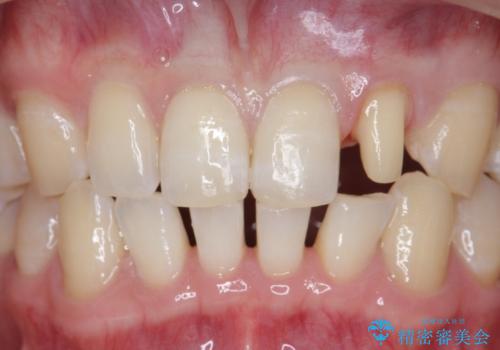

- 上顎前歯のすきっ歯が気になるといらっしゃった方の症例です。

上顎前歯のみの治療を希望されたので、部分矯正を行いました。

左上2の矮小歯はオールセラミッククラウンによる補綴を行いました。

今回用いたオールセラミッククラウンは、ジルコニアフレームという白い素材の上にセラミックを盛っているため審美性が非常に高いのが特徴です。

またジルコニアは人工ダイヤモンドの材料にも使われているほど高い強度を持っており、そのためオールセラミッククラウンは審美性だけでなく、奥歯やブリッジの補綴も可能とするクラウンです。